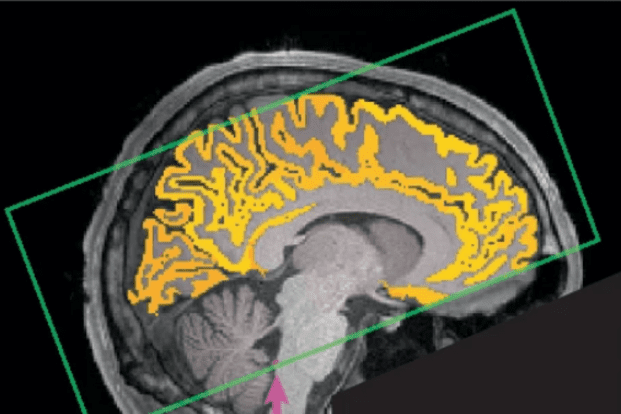

Rappresentazione grafica del circuito chiuso in cui si muove il liquido cerebrospinale (fonte: Yang et al, Nature Neuroscience, 2025)

Alla base degli effetti di una nottata in bianco, come cervello annebbiato e difficoltà a mantenere la concentrazione, ci sono ondate di liquido cerebrospinale, il liquido che avvolge il sistema nervoso centrale per proteggerlo, nutrirlo e per rimuovere le sostanze di scarto. Lo indica lo studio del Massachusetts Institute of Technology pubblicato sulla rivista Nature Neuroscience.

Quando si dorme il liquido cerebrospinale si muove in un circuito chiuso nel quale si distribuisce nelle cavità che si trovano tra le meningi e che avvolgono il cervello. In questo modo favorisce l’eliminazione delle sostanze di scarto. Se però non si dorme abbastanza, questa operazione di depurazione viene comunque fatta quando si è svegli, con la conseguenza di momentanei cali di attenzione.

I ricercatori coordinati da Laura Lewis hanno reclutato 26 volontari, che sono stati studiati tramite encefalogramma e risonanza magnetica funzionale sia dopo una notte di riposo che dopo una notte senza dormire. Durante i cali di attenzione dovuti a deprivazione del sonno, gli autori dello studio hanno osservato cambiamenti fisiologici che si verificano contemporaneamente, il più importante dei quali riguarda il flusso di liquido cerebrospinale.